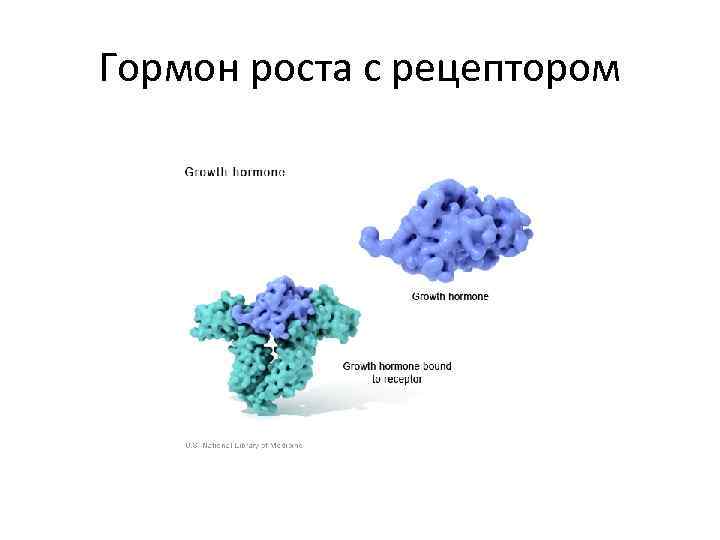

Гормон роста с рецептором

Гормон роста с рецептором